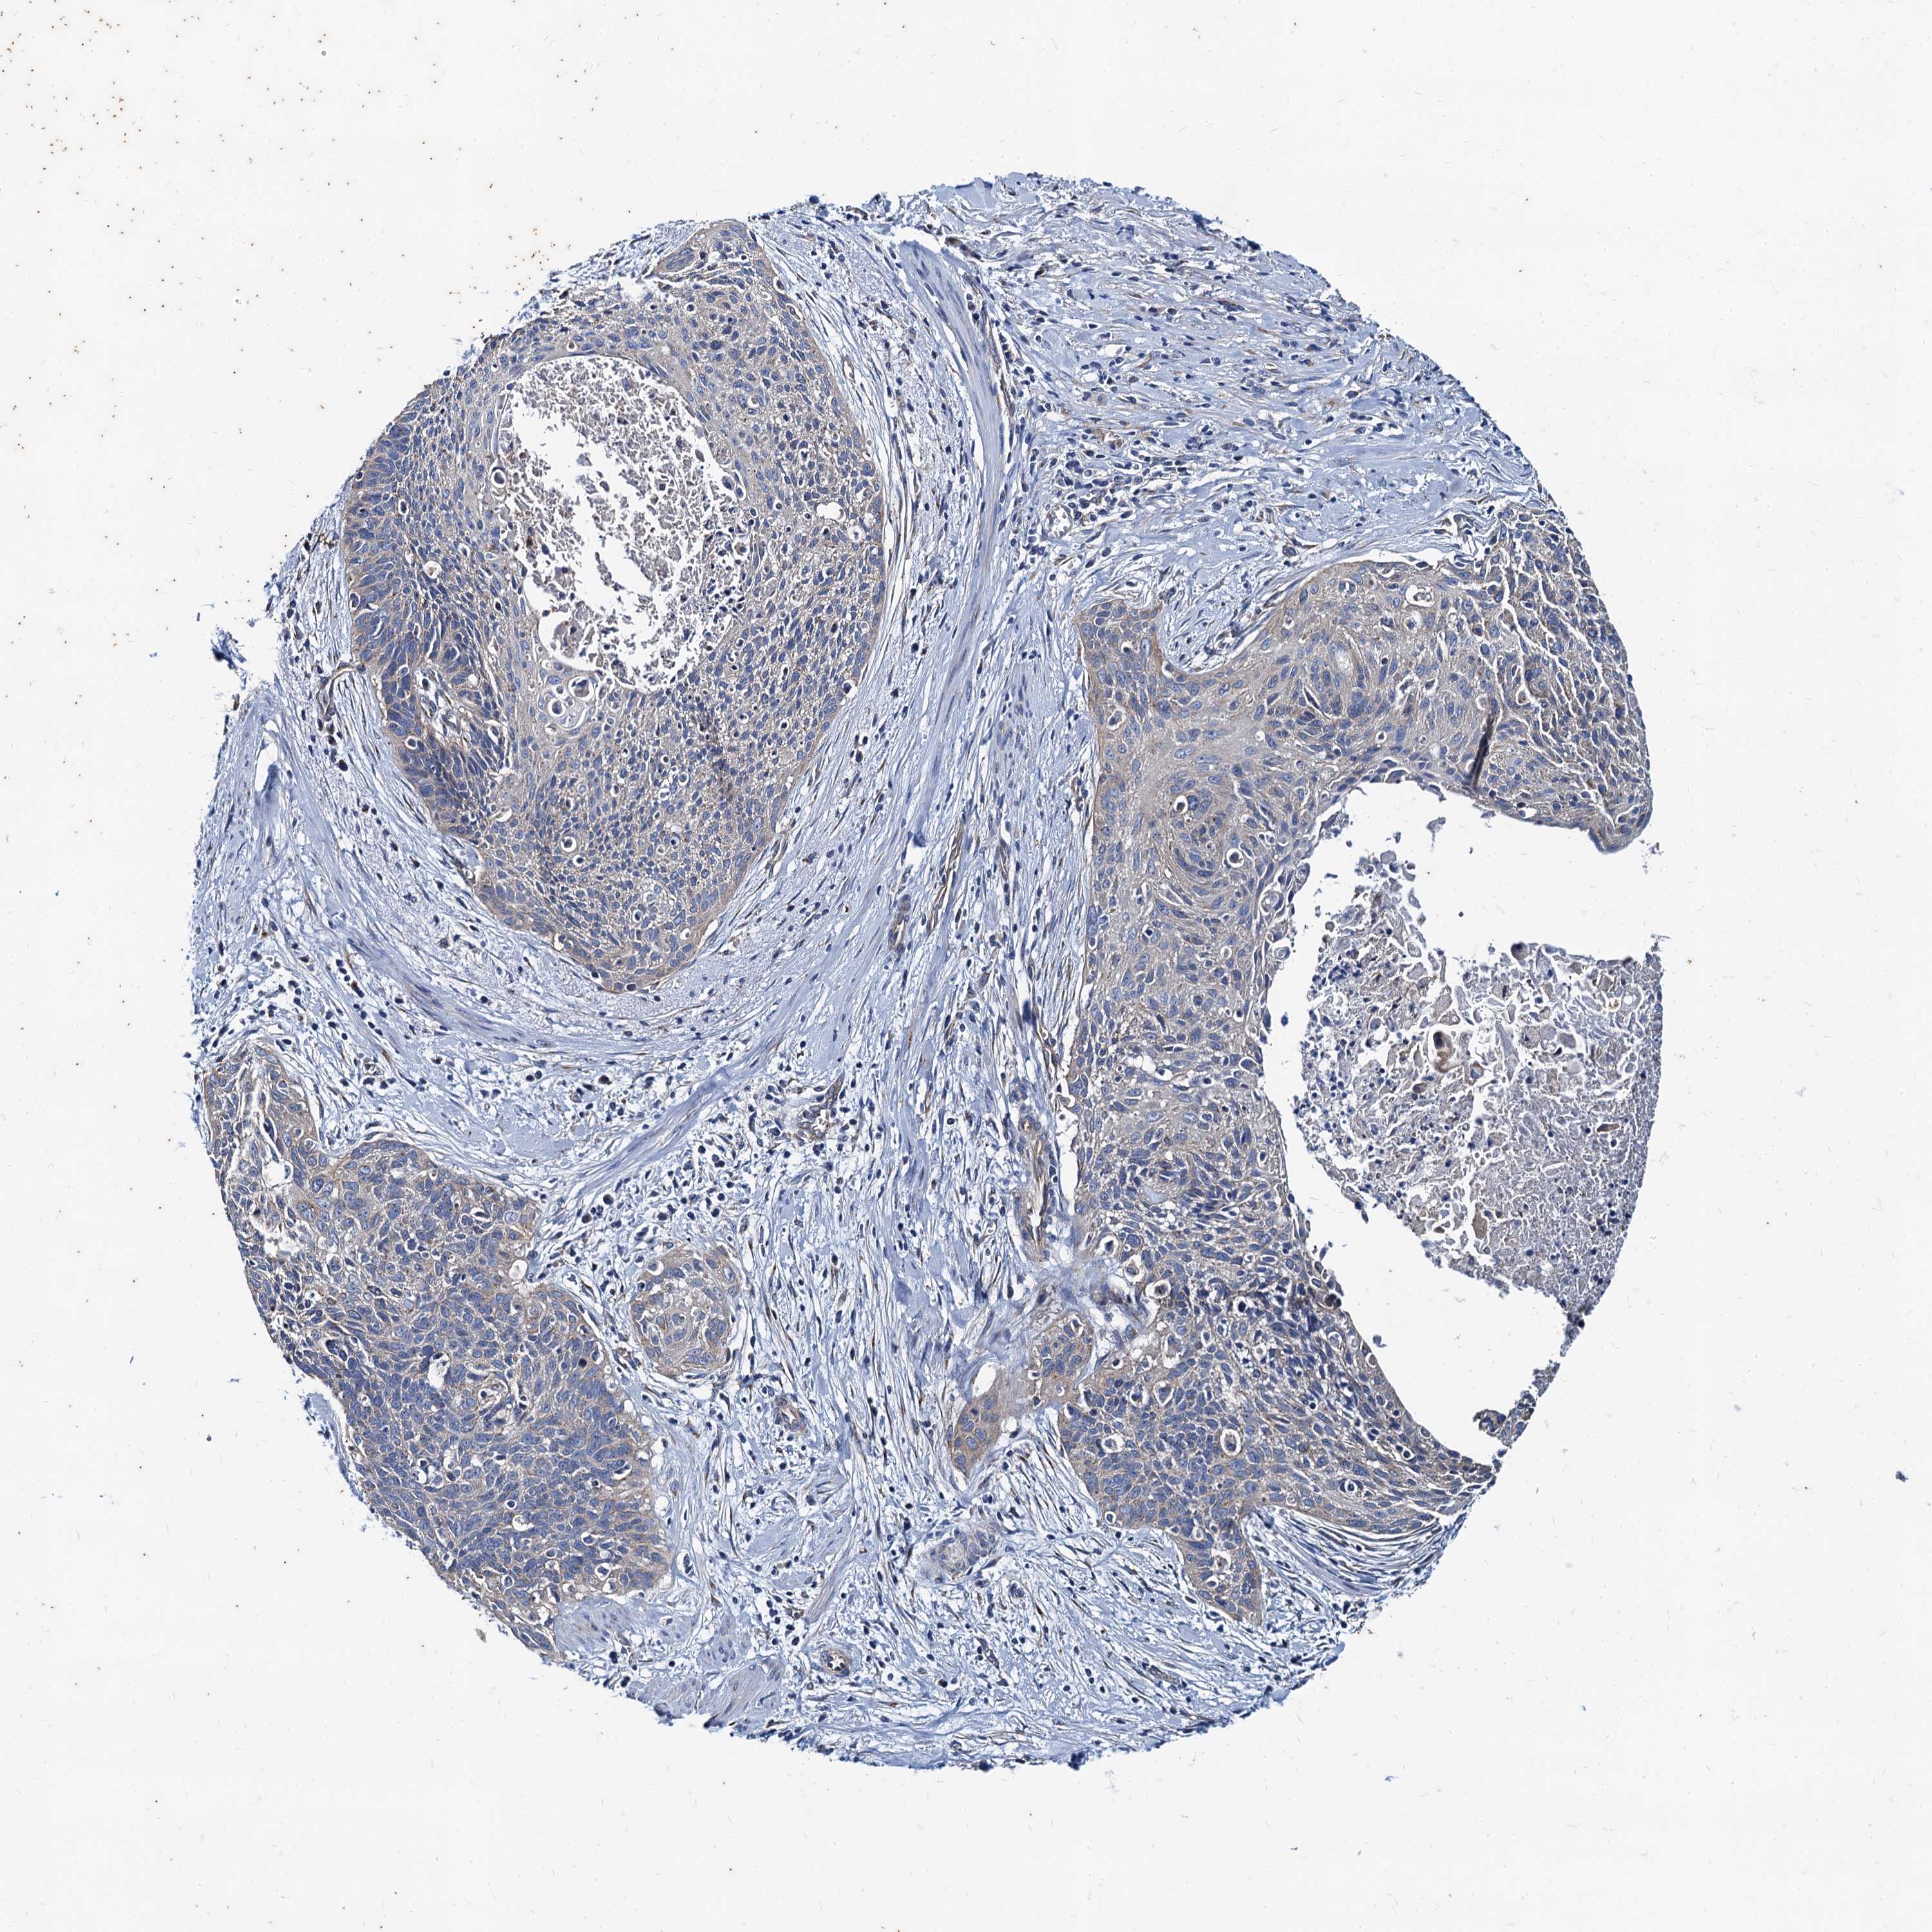

CERVICAL CANCER - Protein expressioni

A mouse-over function shows sample information and annotation data. Click on an image to view it in a full screen mode. Samples can be filtered based on level of antibody staining by selecting one or several of the following categories: high, medium, low and not detected. The assay and annotation is described here.

Note that samples used for immunohistochemistry by the Human Protein Atlas do not correspond to samples in the TCGA dataset.

Antibody stainingi

Antibody staining in the annotated cell types in the current human tissue is reported as not detected, low, medium, or high, based on conventional immunohistochemistry profiling in selected tissues. This score is based on the combination of the staining intensity and fraction of stained cells.

Each image is clickable and will lead to virtual microscopy that enables deeper exploration of all samples and also displays staining intensity scores, fraction scores and subcellular localization as well as patient and tissue information for each sample.

Antibody HPA041367

Antibody HPA076267

Staining

High

Medium

Low

Not detected

Intensity

Strong

Moderate

Weak

Negative

Quantity

>75%

75%-25%

<25%

None

Location

Nuclear

Cytoplasmic/membranous

Cytoplasmic/membranous,nuclear

Squamous cell carcinoma, NOS

Adenocarcinoma, NOS